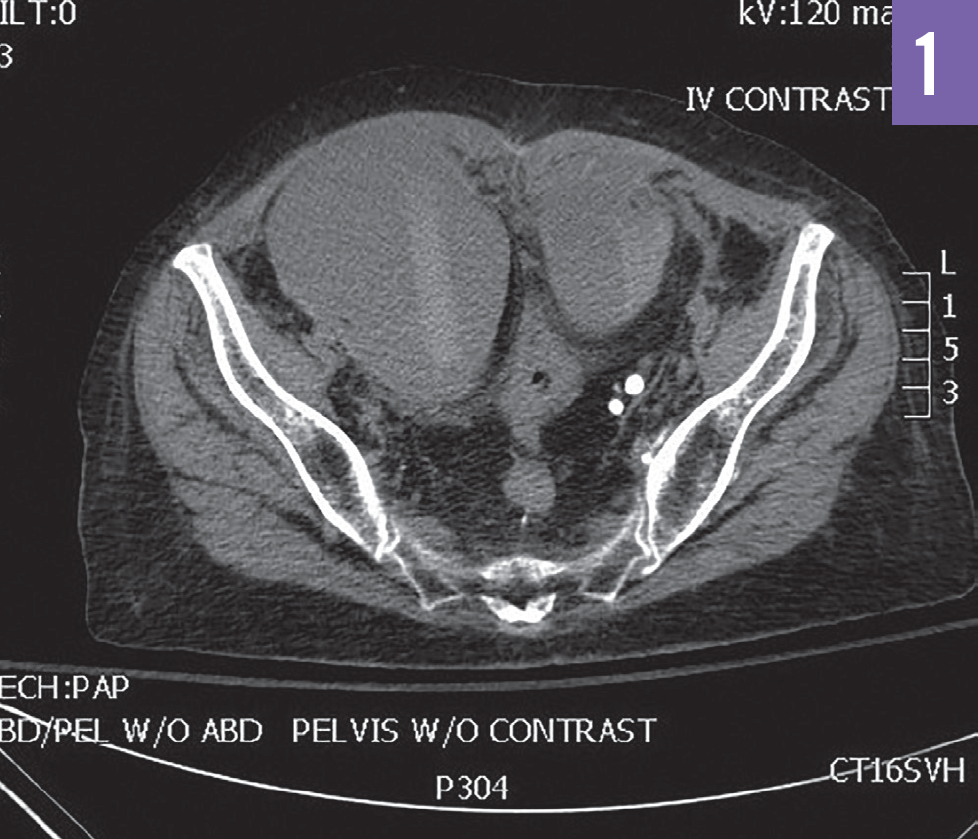

Ricky Kortyna, MMS, PA-C; Emily Murphy, MPAS, PA-C

A 36-year-old woman was seen in the emergency department secondary to the acute onset of right lower-quadrant pain.

06/22/2020